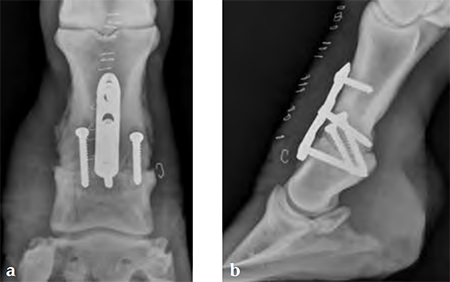

Compression across the joint was achieved by placing the abaxial transarticular 5.5 mm cortical screws in lag fashion, then using the cortex screw in the load position of the proximal combination hole. The screws on either side of the joint are 5.0 mm locking screwsthe most distal screw is placed first, then the cortex screw is used to provide dynamic compression and the final locking screw is placed.

Knox PM, Watkins JP (2006) Proximal interphalangeal joint arthrodesis using a combination plate-screw technique in 53 horses (19942003). Equine Vet J; 38:538542.